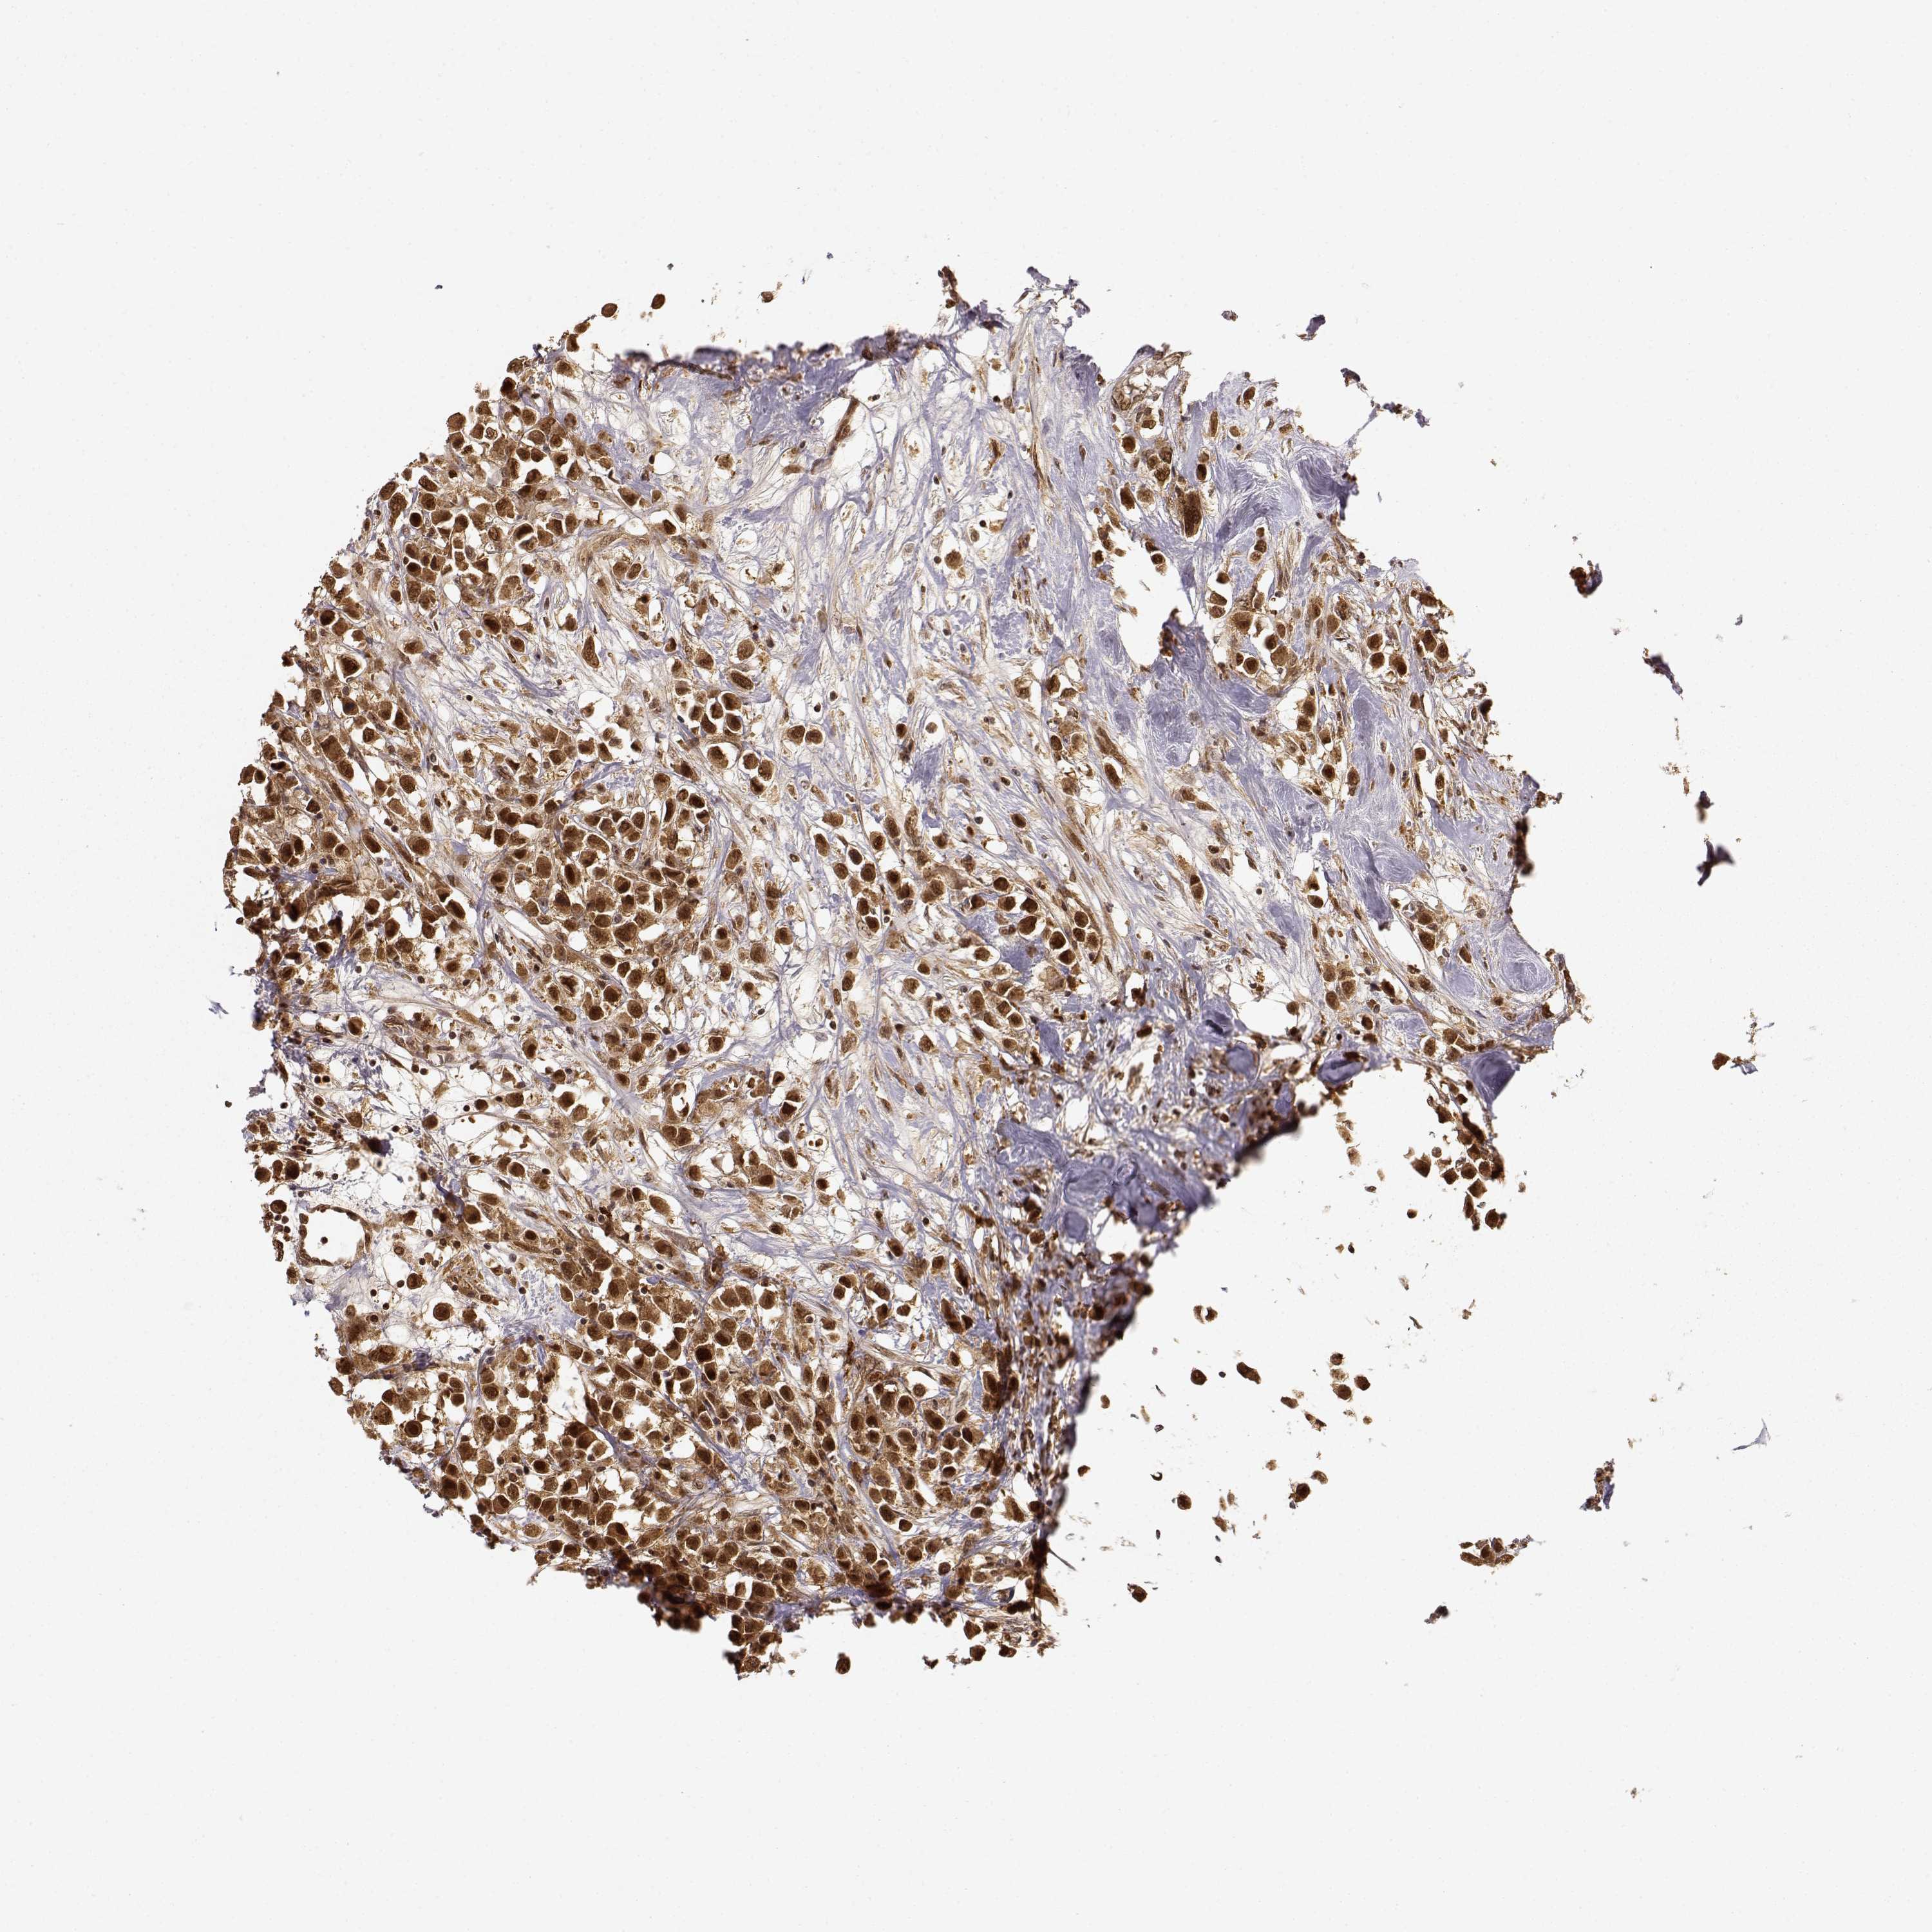

CANCER BREAST CANCER Show tissue menu

BRCA TCGA BRCA VALIDATION PROTEIN EXPRESSION